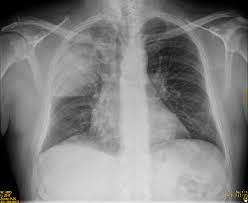

Relación entre los resultados de la radiografía de tórax y el inicio del tratamiento antibiótico en el tratamiento de la neumonía adquirida en la comunidad por médicos generales

04 diciembre 2024

En los pacientes con sospecha de neumonía adquirida en la comunidad (NAC), los médicos de cabecera tuvieron sistemáticamente en cuenta los resultados de las pruebas de respuesta positiva para iniciar el tratamiento antibiótico y tuvieron mucho menos en cuenta las pruebas de respuesta negativa. Estos resultados justifican la aclaración de qué se debe hacer en los casos de sospecha clínica de NAC sin confirmación radiológica. The Annals of Family Medicine, noviembre de 2024,